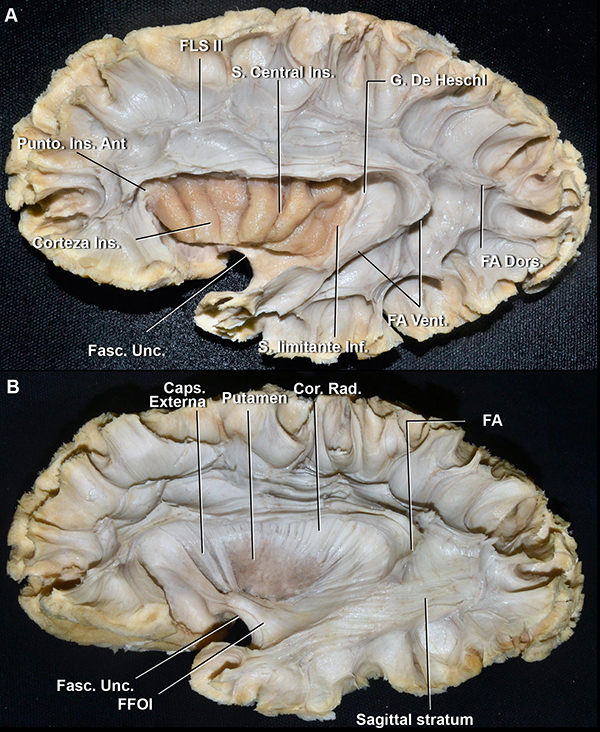

Las fibras blancas más relevantes que se relacionan con el opérculo frontoparietal son las fibras de asociación del fascículo longitudinal superior (FLS) y el fascículo arcuato (FA). El FLS está constituido por fibras que conectan al lóbulo frontal con el parietal. Tiene tres partes, desde lo más profundo a lo más superficial: FLS I, II y III, que se correlacionan superficialmente con el giro frontal superior, medio e inferior, respectivamente. El FA está constituido por fibras que conectan a los lóbulos frontal y temporal, pasando por el lóbulo parietal inferior. El FA tiene un segmento ventral y otro dorsal. El segmento ventral comienza en el tercio medio de los giros temporales superior y medio, pasa a través de la parte inferior del giro supramarginal y termina en el giro frontal inferior. En el opérculo frontoparietal, tiene un curso en la profundidad del FLS III. El segmento dorsal comienza en el tercio posterior del giro temporal medio e inferior, recorre a través de la parte inferior del giro angular y luego se ubica en la profundidad del FLS II para finalizar en el giro frontal inferior y medio (Figura 13A).24

El limen insular es un área anatómica arqueada, medial al polo insular, que yace sobre al fascículo uncinado y se extiende desde el punto en el que el giro largo insular posterior se encuentra con el polo temporal, hasta los giros frontoorbitarios (Figura 13A). El fascículo uncinado (FU), junto con el fascículo fronto-occipital inferior (FFOI) componen la parte ventral de la cápsula externa. El FFOI está constituido por fibras que conectan a los giros frontales medio e inferior con el lóbulo occipital. Las fibras del FFOI comienzan en el lóbulo frontal, en un plano profundo al FA, pasa profundo al punto insular anterior, posterior al FU y luego, cursando a través del giro temporal superior y medio, alcanza la parte posterior de los lóbulos parietal y occipital. El FU conecta estructuras temporales y frontales paralímbicas: el polo temporal con las áreas orbitofrontales y septal (Figura 13).24

Figura 13: A. Disección de fibras blancas de lateral a medial de un hemisferio izquierdo. Se removió la sustancia gris cortical y las fibras intergirales, excepto la corteza insular superior. Se removió el opérculo frontoparietal para exponer las fibras de asociación largas: el fascículo longitudinal superior y el arcuato. El limen insular es un área anatómica que yace sobre el fascículo uncinado. B. Mismo espécimen que en A. Se removió la corteza insular, la cápsula extrema y el claustro, así como también, el segmento temporal del fascículo arcuato. Se disecó la parte dorsal de la cápsula externa para exponer al putamen, dejando unas pocas bandas de la misma en la parte más anterior. FLS: fascículo longitudinal superior; FA: fascículo arcuato; Fasc. Unc.: fascículo uncinado; S: surco; G: giro; Vent: ventral; Dors: dorsal; Inf: inferior; Ins: insular; Ant: anterior; Caps: cápsula; Cor: corona; Rad: radiata; FFOI: fascículo fronto-occipital inferior.